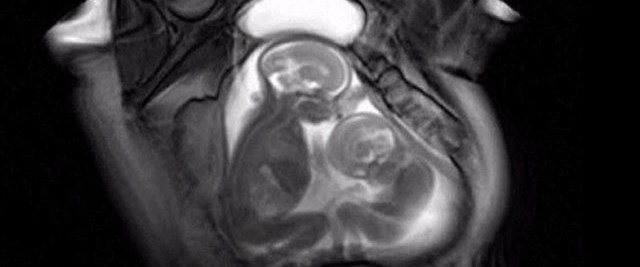

cin de anne karnindaki ikizlerin kavgasi goruntulendi

anne karninda yer kavgasi ntv